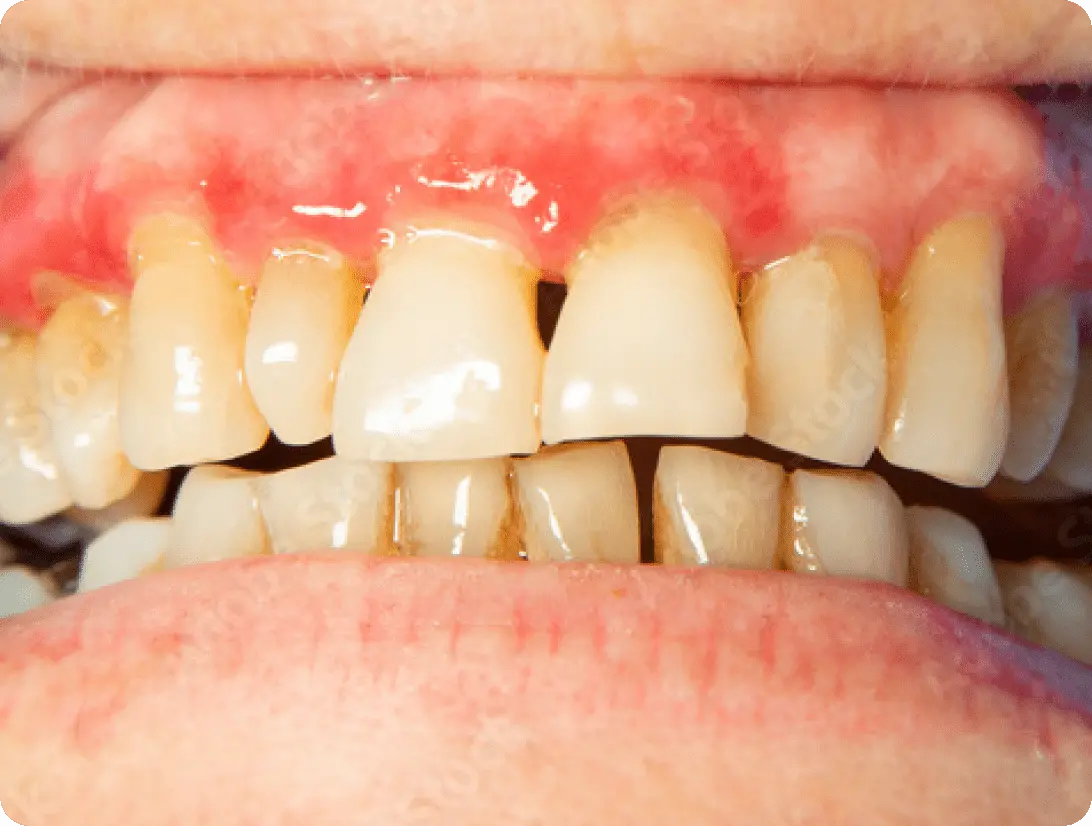

歯周病治療

痛みのないまま静かに進行し

歯が失われる病気

日本人の歯を失う原因の第1位と言われる歯周病。30代以上の3人に2人が歯周病と言われています。歯肉が赤くなったり、腫れたりしますが痛みはほとんどの場合ありません。気づかないうちに進行し、歯を抜かなければならない場合もあります。手遅れになる前に早めの対処が必要です。